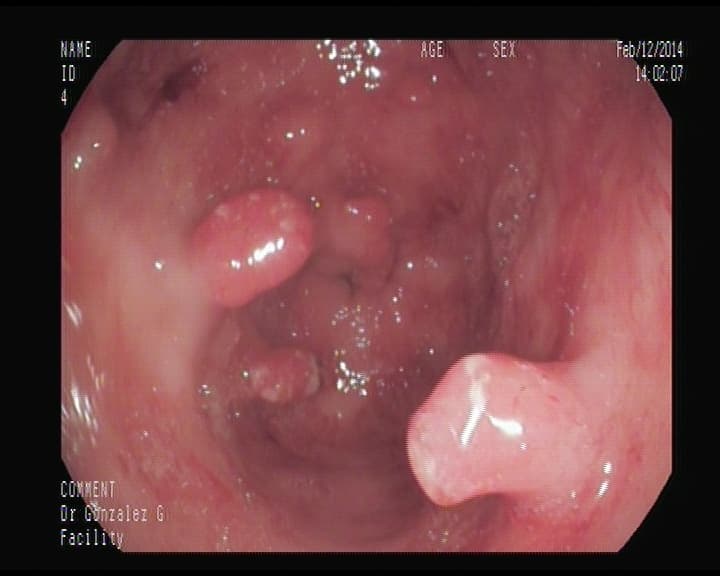

Pólipo adenomatoso, con pedículo ancho

Deben ser resecados para su analisis histólogico, y confirmar que es pólipo que se transformaría en cáncer. Esto no da sintomatología, una sangre oculta en heces, nos puede inducir a realizar colonoscopia y detectarlos.